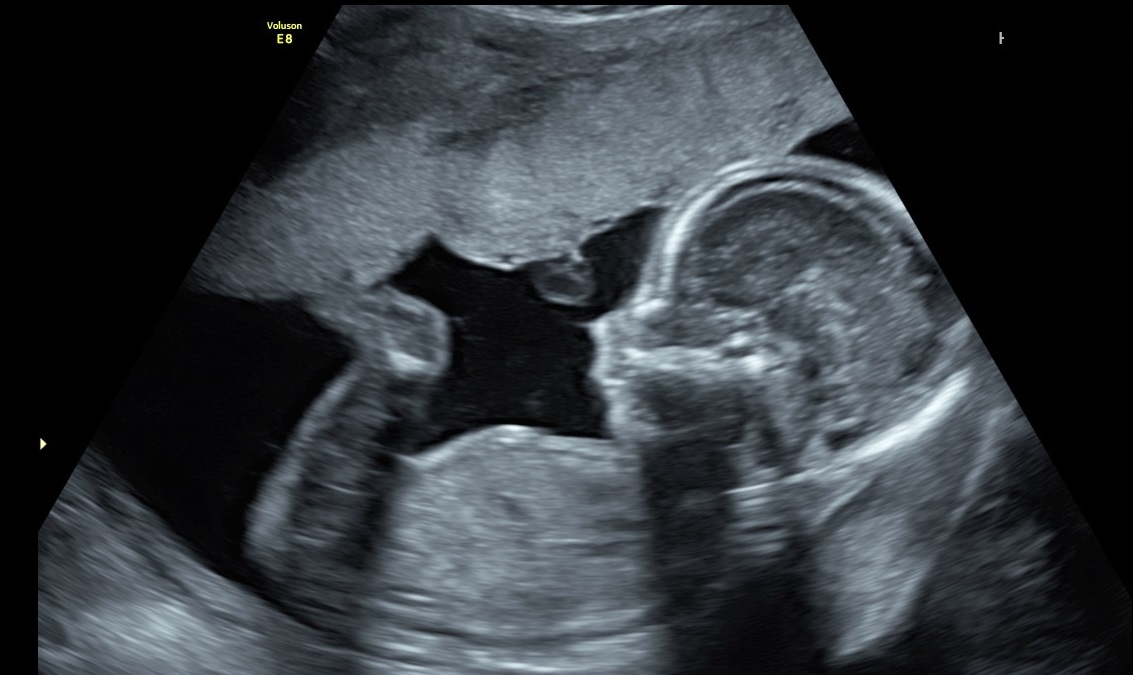

Fetal Echocardiography is a test similar to ultrasound. It allows the doctor to see the structure and function of the baby’s heart in detail. It also enables the doctor to see blood flow through the fetal heart and cardiac rhythm.